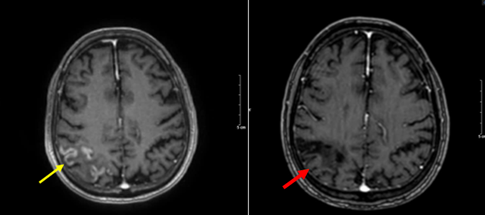

- Chụp MRI sọ não (tháng 9/2024):

Hình 4: Dày, ngấm thuốc màng não kèm theo phù não vùng chẩm P kích thước 60*40mm trên xung T2 (mũi tên đỏ), và xung T1 tiêm thuốc (mũi tên vàng)

Hình 10: Hình ảnh cộng hưởng từ sọ não trên xung T1 tiêm thuốc: hình ảnh tổn thương dày, ngấm thuốc màng nào (mũi tên vàng) sau 6 đợt điều trị không còn tổn thương ngấm thuốc màng não (mũi tên đỏ)